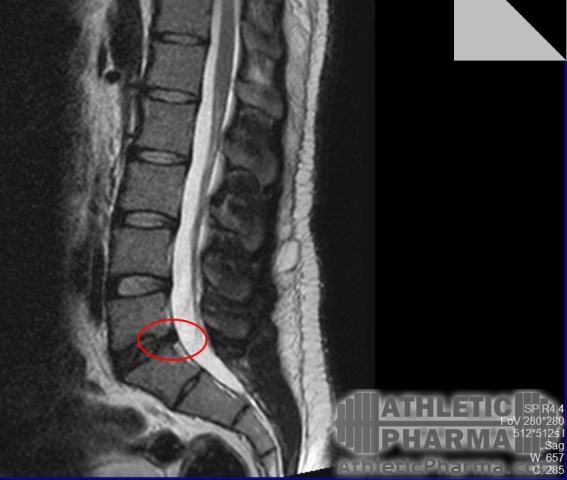

Сделал МРТ(сейчас 90кг) межпозвоночная грыжа 5мм в сегменте L5-S1, остеохондроз, признаки спондилоартроза поясничного отдела; протрузия в грудном отделе до 3мм.

med_gallery_26_2_24020.jpg